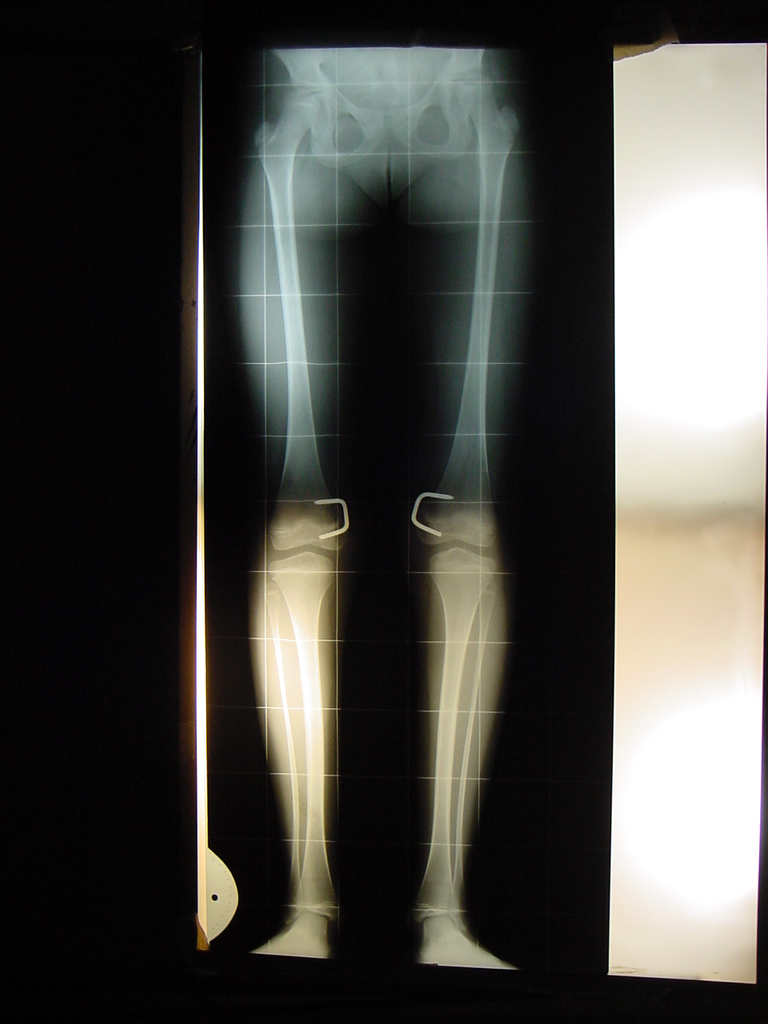

Modulación del crecimiento en osteodistrofia renal. [Growth modulation in renal osteodystrophy]